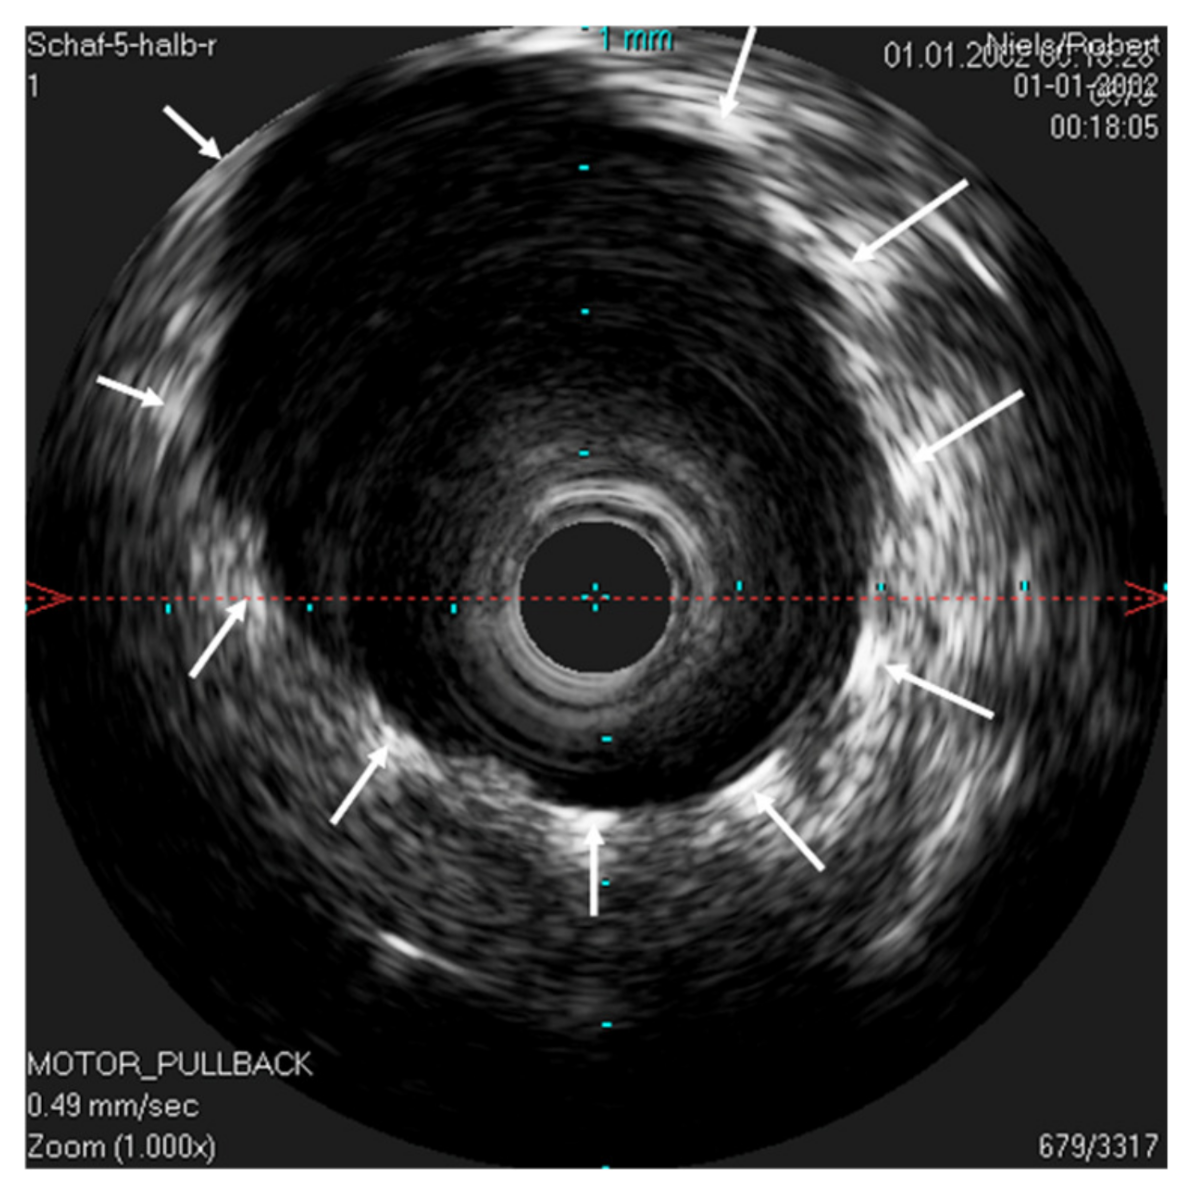

Figure 7. Ultrasound image of the stented ET. The lumen of the ET is opened by the unfolded stent. The IVUS probe is located in the lumen of the stent. The stent struts can be seen echogenically, and sonic extinction is marked with white arrows. Note: the ET was flooded with water before the scan to allow for sonic coupling.